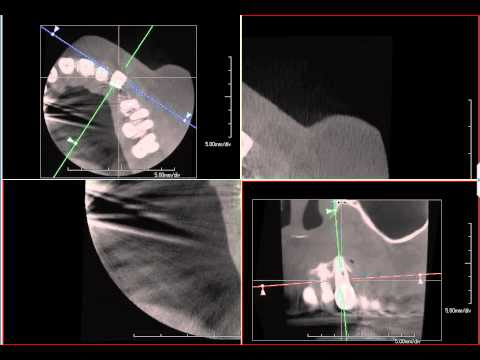

Como confirmar a fratura radicular .... Tempo de tecnologia

Análise Tomográfica de Canal Atresiado